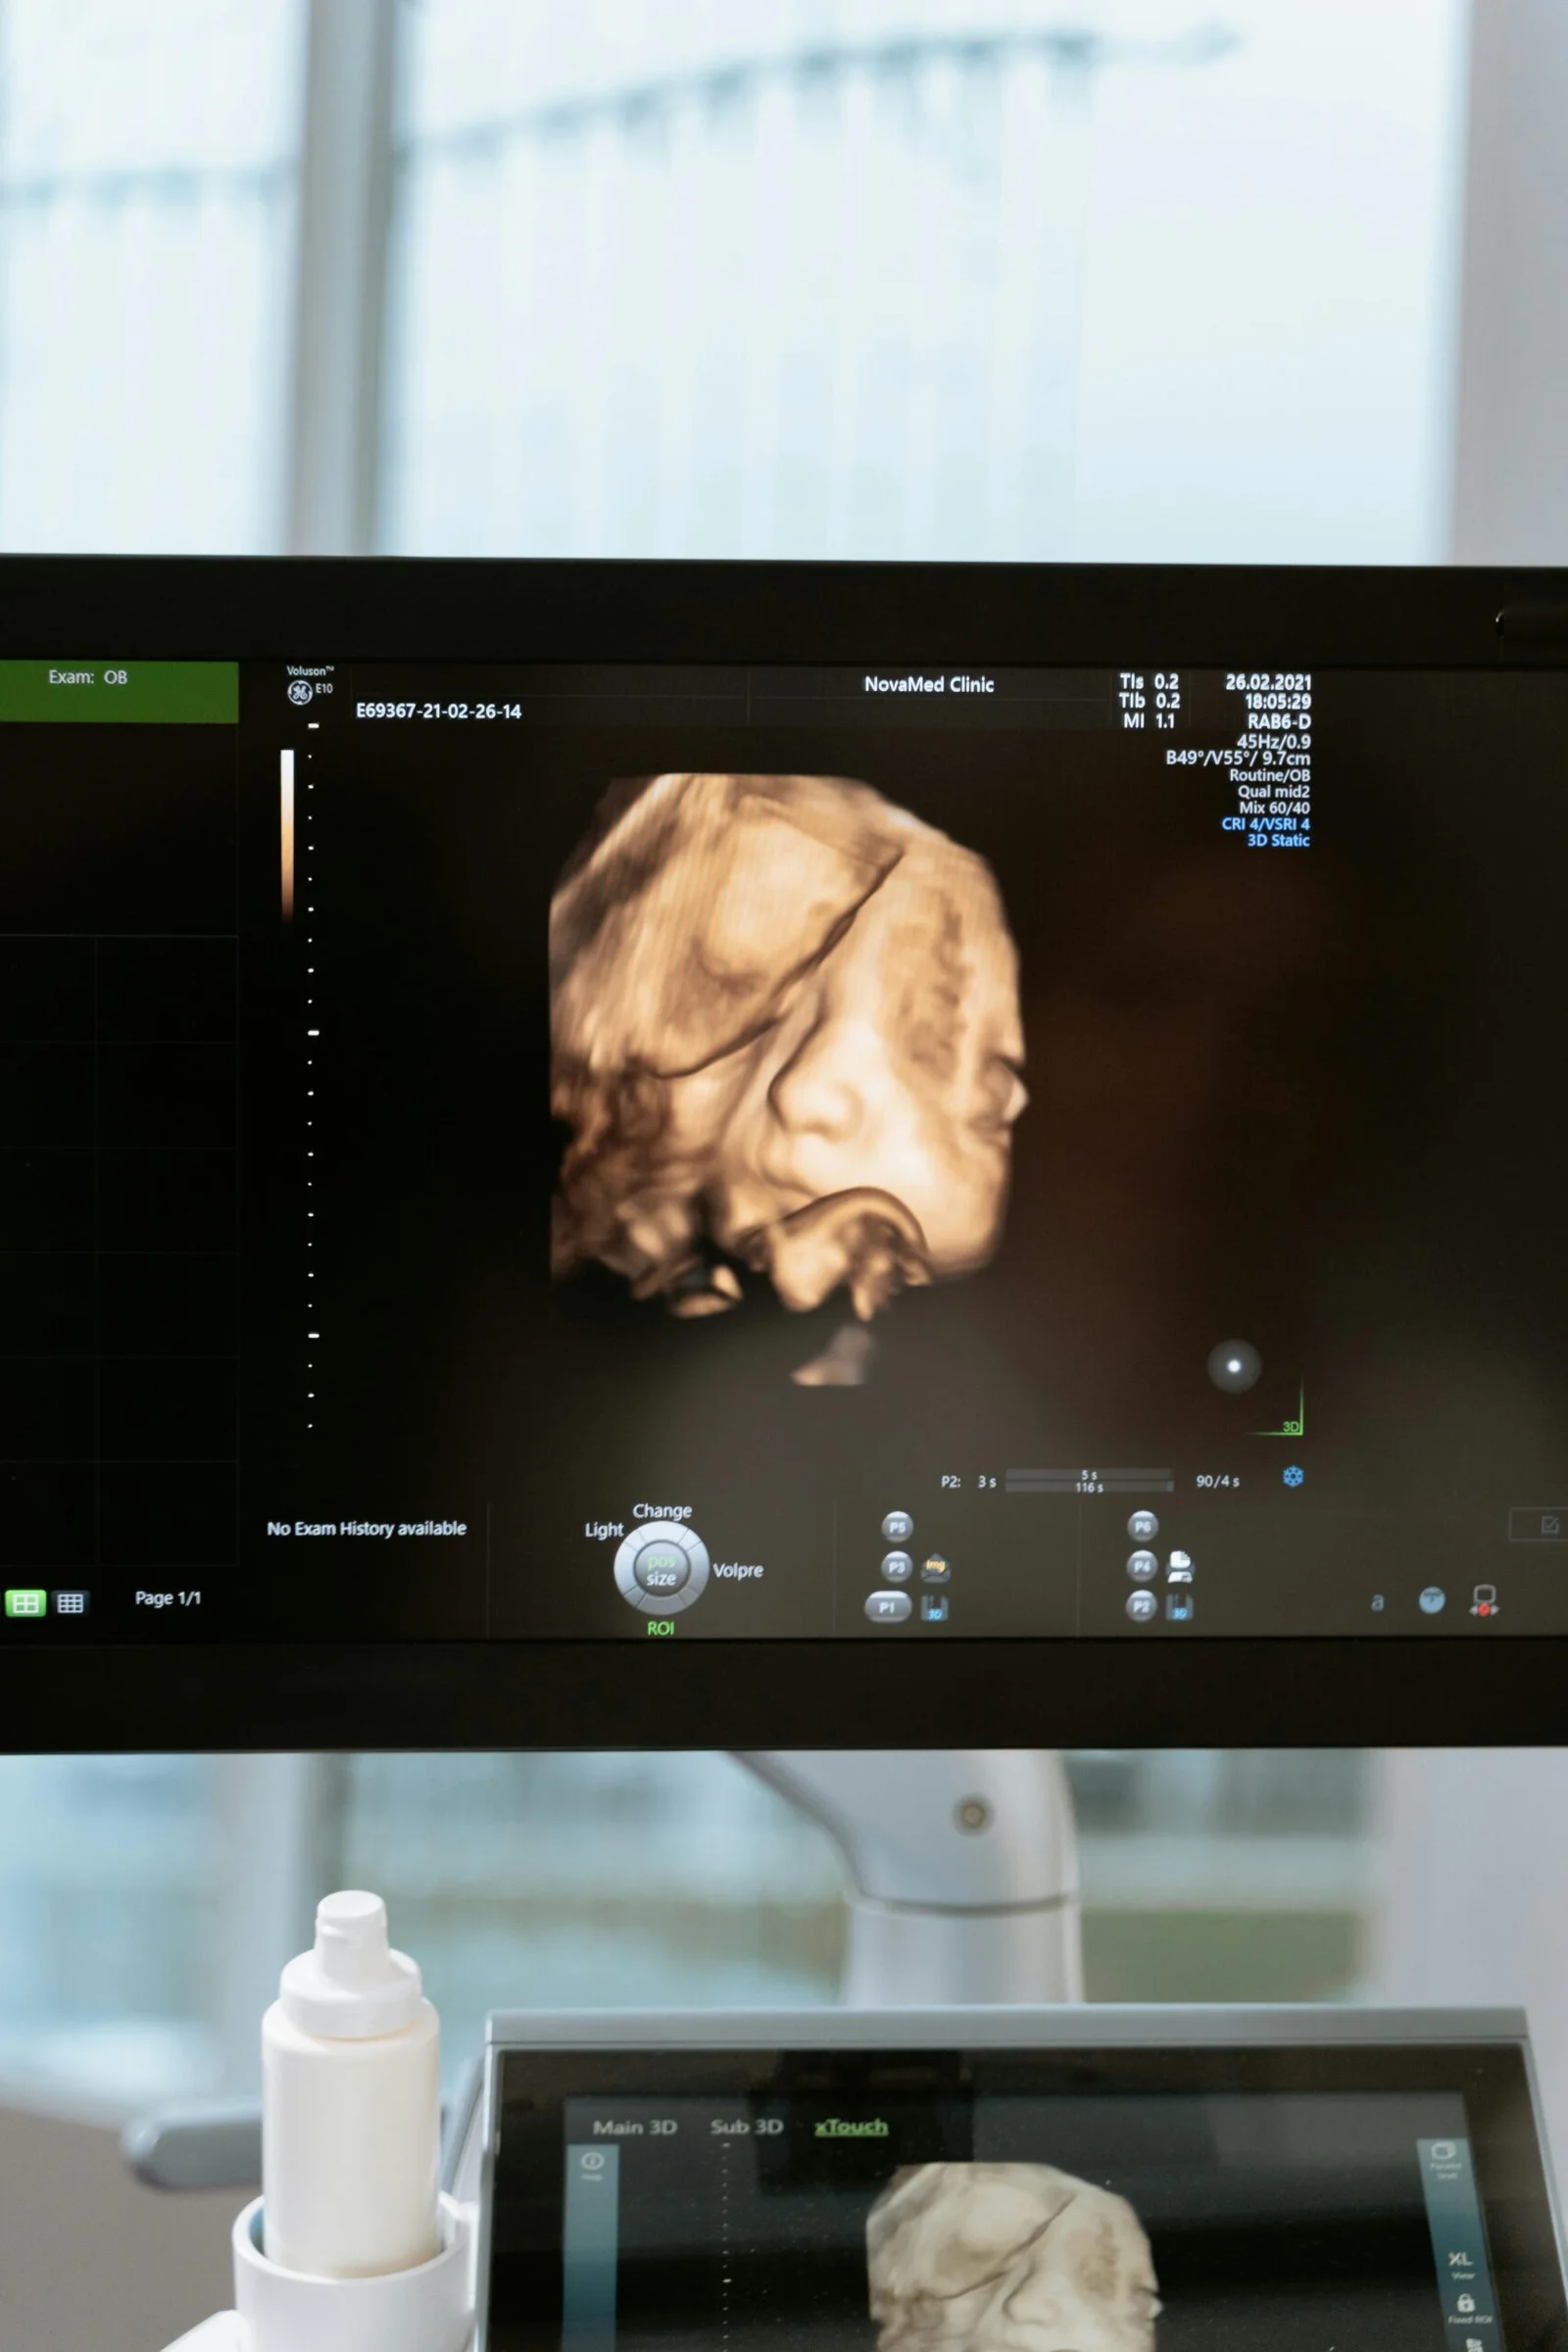

A special bonding scan designed to help you connect with your baby in a relaxed and memorable way. Approximate scan time 30 minute

£232.50

For a special 4D session to see your baby’s movements and facial features in real time. Approximate scan time 15 minute

£127.50

For a special 4D session to see your baby’s movements and facial features in real time. Enjoy extra time bonding with your baby during this extended 4D imaging session. Approximate scan time 25 minute

£195.00